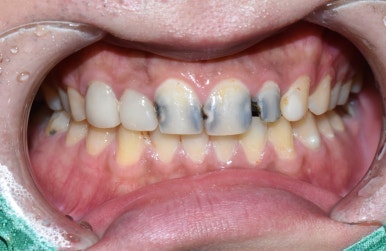

오늘은 치아가 "너무 많이 썩어서 부러졌어요, 앞니가 너무 많이 썩었는데 살릴 수 있을까요?"라는 용건으로

3년만에 찾아오신 환자분의 케이스입니다.

↑이번 2024년에 이 상태로 내원하셨는데요

사실 이분은 3년도 더 전에 2021년에 저희 치과에서 심한 앞니 충치 몇개를 치료 받으신 분입니다. 그 때 치료받은 치아 말고 다른 치아들은 다 썩어서 이런 상태로 오셨네요

환자분의 동의를 얻고 찍은 영상과 사진입니다

충치를 제거했더니 남는 치아부분이 이렇게 밖에 없는 상태ㅠㅠ

20대 환자분인데도 어떻게 이런 앞니로 학교다니고 사회생활 하셨냐며...

대문이 2개는 신경치료하고 앞니 크라운 2개 하셔서 2개는 크라운까지 완성된 상태구요.

사진상 오른쪽(환자분 기준으로는 왼쪽) 두번째 치아는 아직 크라운을 못하시고

신경치료 하고 사회생활은 하셔야하니 현재 레진으로 만들어놓은 임시 상태인데

환자분이 시간이 없이 너무 바쁘셔서 일단 다음번에 크라운 작업 시작하기로 한 상태입니다.

어쨌든 사회생활은 하실만큼 만들어놓은 상태죠.

처음과 비교하면 보기에도 훨씬 깨끗하고 좋아졌습니다.

앞니 크라운 2개와 옆치아 1개는 임시레진상태